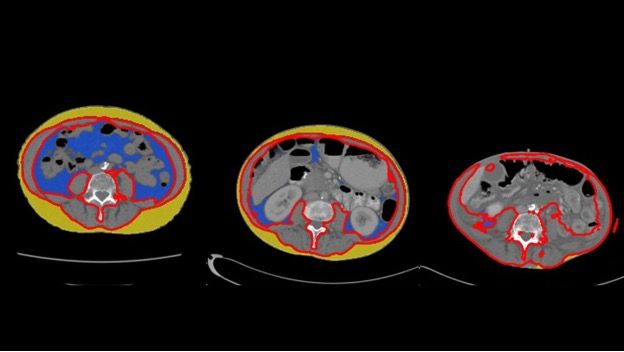

Dr. Bi teamed up with Derk Klatte, M.D., Ph.D., and Michael Wallace, M.D., to examine medical records of patients with a common type of pancreatic cancer known as pancreatic ductal adenocarcinoma (PDAC) who had been diagnosed at Mayo Clinic between 2002 and 2021. They analyzed abdominal CT scans and blood tests taken up to three years before the patients were diagnosed. Using advanced algorithms developed by data scientist Alex Weston, Ph.D., the researchers measured changes in body fat, muscle and bone, as well as shifts in blood-based biomarkers like cholesterol and glucose levels.

The findings, published in the journal Clinical Gastroenterology and Hepatology, revealed changes in a variety of physiological and metabolic measurements. The researchers observed significant reductions in both fat surrounding the organs (visceral fat) and the fat under the skin (subcutaneous fat) as patients approached their diagnosis date. In addition, patients exhibited a notable drop in serum lipids — fats found in the blood — such as low-density lipoprotein (LDL), total cholesterol and triglycerides.

Conversely, the study found that blood glucose levels increased up to three years before patients were diagnosed with pancreatic cancer, confirming a link previously described by Mayo Clinic gastroenterologist Suresh Chari, M.D. Additional findings revealed that patients also experienced a loss of muscle mass and bone volume, which became more pronounced in the last six months before their cancer was detected.

Abdominal CT scans in the same individual shows profound changes in body composition from 14 months prior (left) to nine months prior (center) to time of pancreatic cancer diagnosis (right).